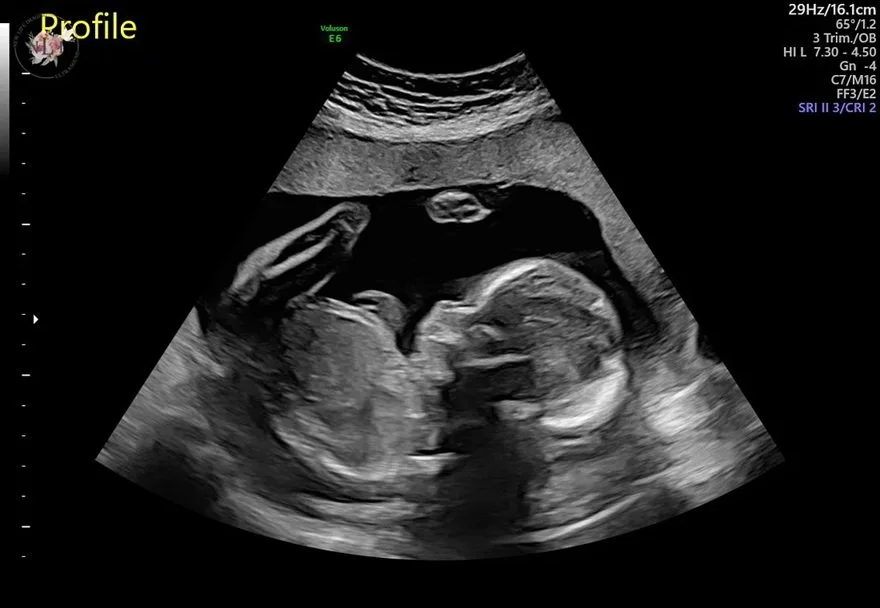

Further, this pregnancy has had multiple minor scares, including struggling to find a heartbeat in week twelve and some bleeding. But by God’s grace, all is well with Mom and baby number three as we enter week twenty-one. That is why we are excited to announce that we are expecting a baby boy, Edmund James “EJ” Garrigan, due in late December of this year!

Edmund James Garrigan, due December 2023. Photo courtesy of New Life Imaging (@newlifeimaginginc on Instagram)

The name “Edmund” means “prosperous, protector,” and “James” means “to follow, to be behind.” We are hopeful our firstborn son proves to be a protector of the innocent and defenseless and one day chooses to follow after the Lord who created Him and preserved his life on the heels of death.